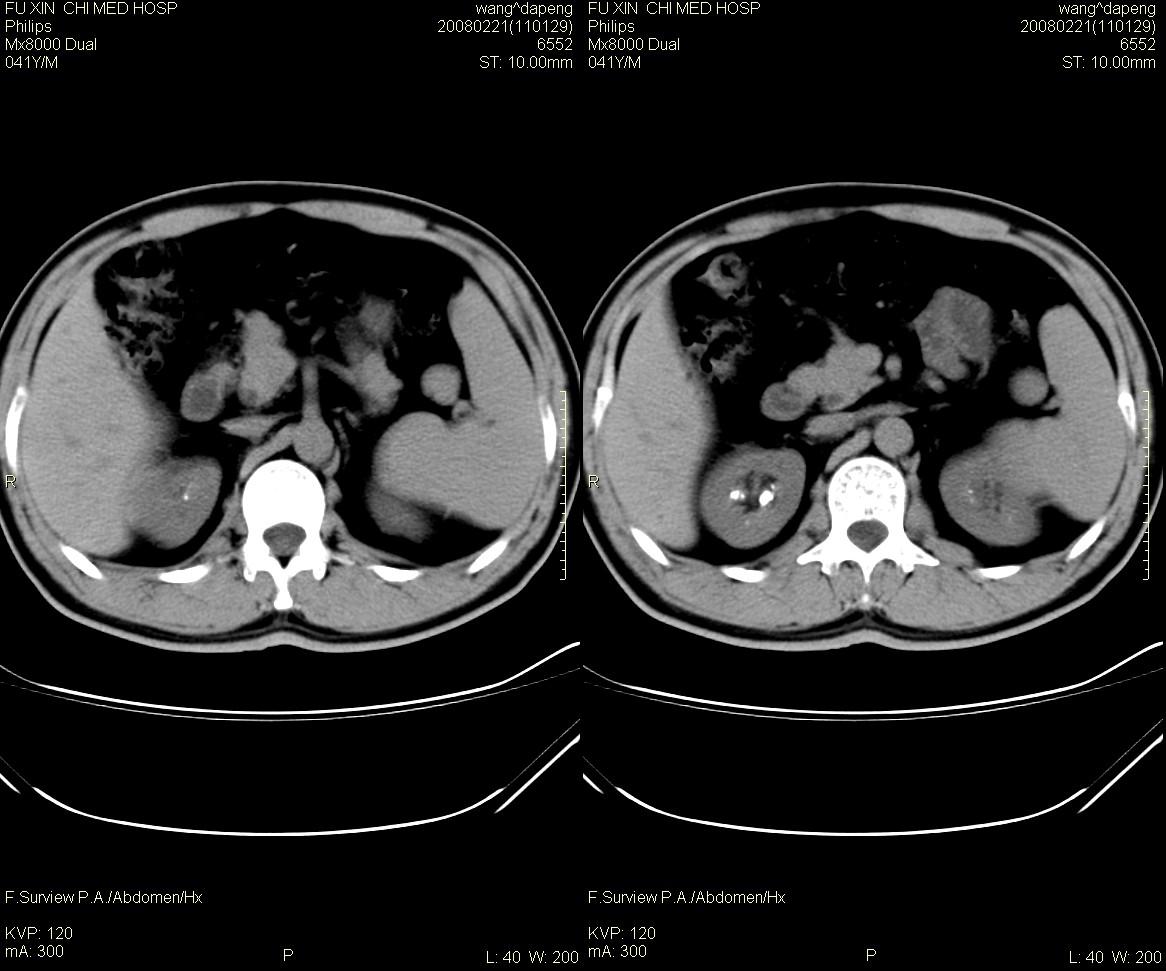

男,41岁,临床发现双肾结石10年。是髓质海绵肾吗?如何确诊。请战友指教。

髓质海绵肾是一种先天性的肾髓质囊性病变, 其特征为肾锥体部乳头管及集合管呈梭形或囊状扩张,并伴发感染和尿路结石形成。在肾标本切面上, 可见髓质中呈海绵状改变。ct平扫表现为肾盏旁锥体内多发小斑点状结石, 成扇形排列.增强扫描后扩张的肾集合管内结石周围有造影剂充盈, 无结石的肾锥体集合管呈条纹状或小囊状造影剂积聚,肾功能正常.

本例支持:髓质海绵肾

海绵肾是先天性的,可能是有遗传倾向的良性肾髓质囊性病变,常于40岁以后发现,易误诊断肾结石和尿路感染。其病理特征是肾小管远端集合小管扩张,形成小囊和囊性空腔,并位于肾盏连接处,易导致结石、感染等。病变一般为双侧性80%的病人部分或全部肾乳头受累。临床上病变局限,轻微者可无明显症状,常见的症状为腰痛、血尿、尿路感染及肾绞痛等。

海绵肾的影像诊断主要靠静脉尿路造影,在平片上表现为双侧肾盏处侧有多发的小结石影。造影后显示肾乳头囊状扩张,内见单发或多发的钙化点,表现为环绕于肾盏、肾盂周围的多数囊腔,形似菜花。ct对海绵肾集合小管囊状扩张的空间分辨率不如ivu高,但对检出其中的小结石较x线敏感。因此,可疑海绵肾的影像诊断应结合上述两种检查。

鉴别诊断:1)肾结石:位于肾盂或肾小盏内,增强后排泌的造影剂常把结石掩盖,较大的结石常使其以远的肾盏发生梗阻性积水。2)肾结核:一般常单侧发生,肾实质内可见单发或多发大小不等、形态不一的囊腔,囊壁有钙化斑,局部肾盏可见不规则的破坏或造影剂充盈不佳,常并发有肾盏、肾盂积水。3)肾乳头坏死:愈合期表现为集合小管内或周围弥散性钙盐沉积,钙化较海绵肾更广泛。